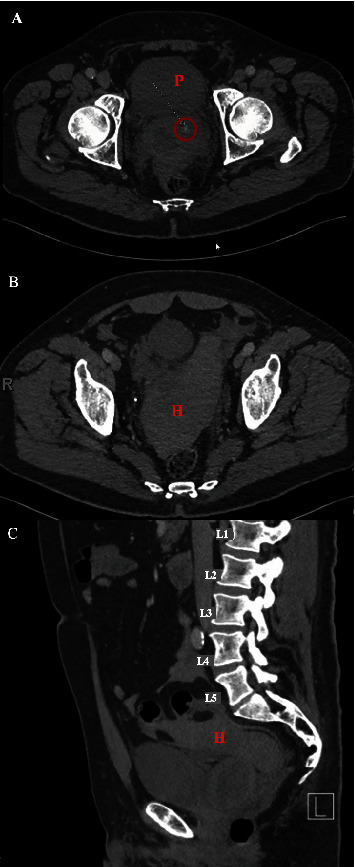

Transperineal prostate biopsy is becoming a popular approach in the diagnosis of prostate cancer. Urethral bleeding and urinary retention are the most common complications. We report a case of intraperitoneal bleeding after transperineal prostate biopsy in a patient with history of focal therapy for prostate cancer. The patient presented with dizziness, abdominal pain, and tenderness a few hours after the procedure. A computed tomography (CT) scan showed intraperitoneal bleeding. He was managed conservatively without needing any interventions or blood transfusion. Intraperitoneal bleeding is a possible, rare, and unexpected complication after transperineal biopsy especially in smaller prostates with prior procedures and scarring.